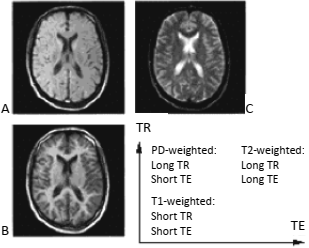

As imagens A, B e C mostradas a seguir são realizadas com diferentes métodos de aquisição, a saber: T1, T2 e densidade protônica.

Com base nas imagens anteriores, é correto afirmar que